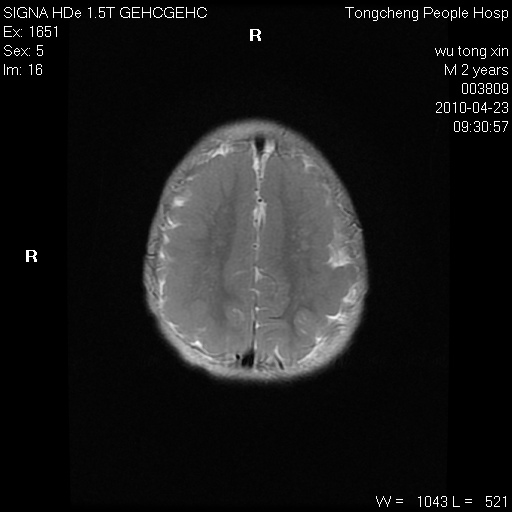

以下是引用赵物学在2010-4-25 12:43:00的发言:[br]巨脑回[br]侧脑室后角低密度影考虑hie或肾上腺脑白质营养不良?[br][br][本贴已被 赵物学 于 2010-4-25 12:51:28 修改过]

以下是引用gaoxiao在2010-4-25 16:54:00的发言:[br]巨脑回畸形。脑白质髓鞘化不良

以下是引用pujunzhi在2010-4-25 21:35:00的发言:[br]考虑 1双侧大脑皮质发育不良 2轻度脑积水 3双侧脑室后角旁片状长t1长t2信号,需继续观察,因为正常小儿此处脑白质的髓鞘化时间可以延迟到4-6岁,才显示正常。